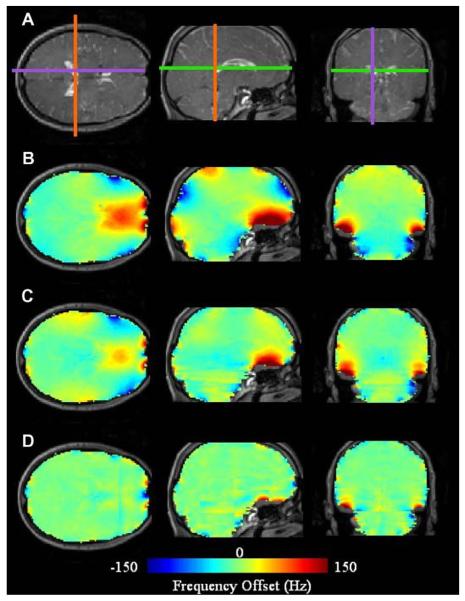

Fig. 13 illustrates significant DSU-utilized homogeneity improvement in axial slices local to the frontal sinuses and auditory cavities at B0 = 4T. Following static global shimming with up to second order shims, the global maps illustrates the severe residual inhomogeneity encountered in the frontal cortex of the brain. Field inhomogeneity of up to 150 Hz can readily be encountered a few centimeters into the brain. The field map acquired using DSU demonstrates significantly reduced frontal lobe inhomogeneity along with slight improvements near the auditory cavities. Improvements are highlighted with white arrows. These results also demonstrate that slice-specific DSU with zeroth through second-order shims cannot perfectly compensate all inhomogeneity in the human brain. The degree of improvement with DSU can also be altered with alterations in ROI definition. For instance, regions of very high inhomogeneity (such as those directly near the sinus and auditory cavities) could be omitted from slice-specific ROIs to allow the available shims to operate more selectively on lower-order inhomogeneity.

Fig. 13.

Homogeneity improvement with whole-slice optimized DSU. Field maps with (DSU) and without (global) dynamic shim changes along with slice-specific histograms for both shim settings. B0 = 4T.

5.1.2.2. EPI

As derived in Section 2.2.1, compared with conventional single-echo Cartesian imaging strategies, the phase-encoded dimension of single-shot EPI have distortion that is multiplicably exacerbated by the number of phase-encoded steps.

B0-induced distortion is often underestimated in EPI images. Distortion whereby pixels inside the brain effectively move to overlapping positions cause an intensity buildup effect that is not always easily distinguished from the underlying pixel shifts. However, this is the most common effect of image distortion. Only when pixels on the boundaries move in such a way so as to distort the outer shape of the brain is distortion obvious to the naked eye.

Such distortion is significant in high-field EPI images at typical imaging bandwidths (100–250 kHz). Using Eq. (28a), the displacement in the phase-encode direction of a given pixel can be related to the measured B0 offset at that pixel. For a 64 × 64 in-plane acquisition with a readout bandwidth of 100 kHz, an image shift of one pixel occurs in the phase-encoding direction for 24.5 Hz of B0 offset. Thus, one could effectively replace the color contrast limits in Fig. 13 with ±6 pixels to uncover how far each pixel will move in the phase-encode direction of an EPI acquisition.

Fig. 15 demonstrates improvement in geometric distortion comparing EPI images with a static global shim and second-order DSU. Improvement in the EPI images depends on slice position. The middle slices show limited improvement due to their initial (global second-order RT shim) lack of significant inhomogeneity. A number of slices show signal recovery and reduced image distortion (as indicated with yellow arrows). However, while DSU does make significant improvements, it is clear that the resulting EPI images still contain residual artifacts.

Fig. 15.

EPI images (64 × 64 in-plane pixels over 25.6 cm × 25.6 cm, 4 mm slices, B0 = 4T, TR = 2500 ms, TE = 25 ms, and readout bandwidth of 100 kHz) under static and dynamic second-order shim settings for axial slices (from left to right). Dotted lines indicate the brain contours as extracted from an undistorted FLASH acquisition (top row). Arrows designate areas of significant image quality improvement.